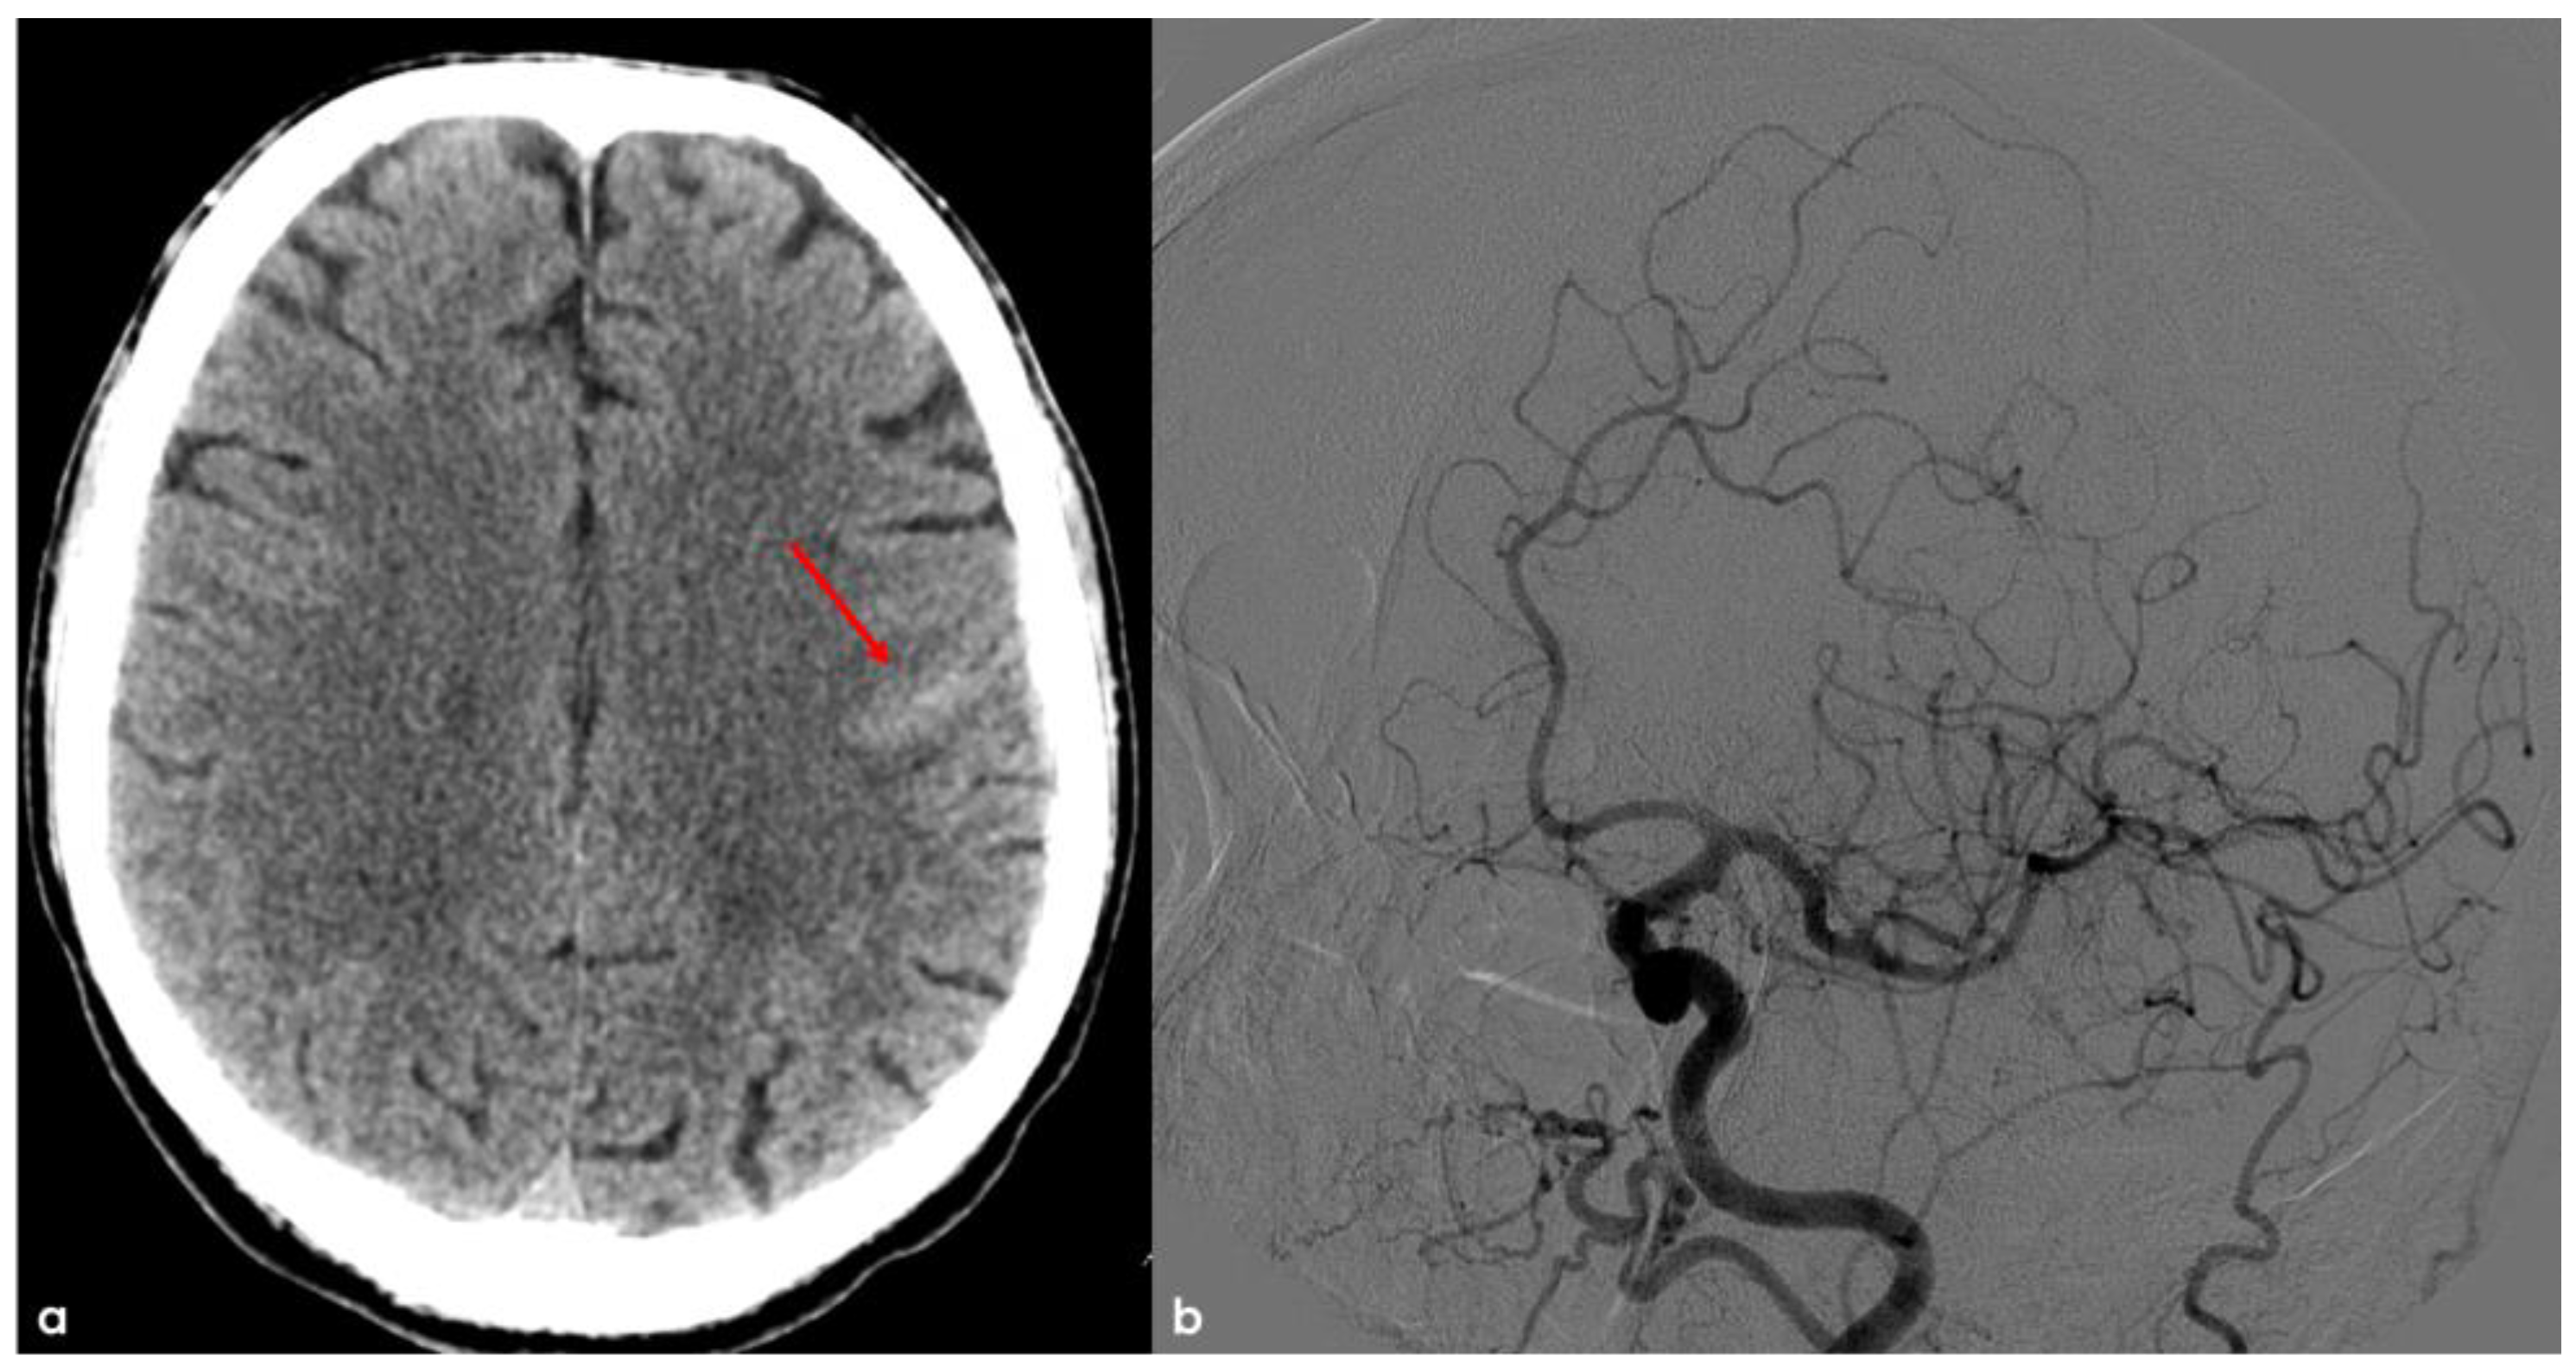

4. December 2015: Ischemic Stroke